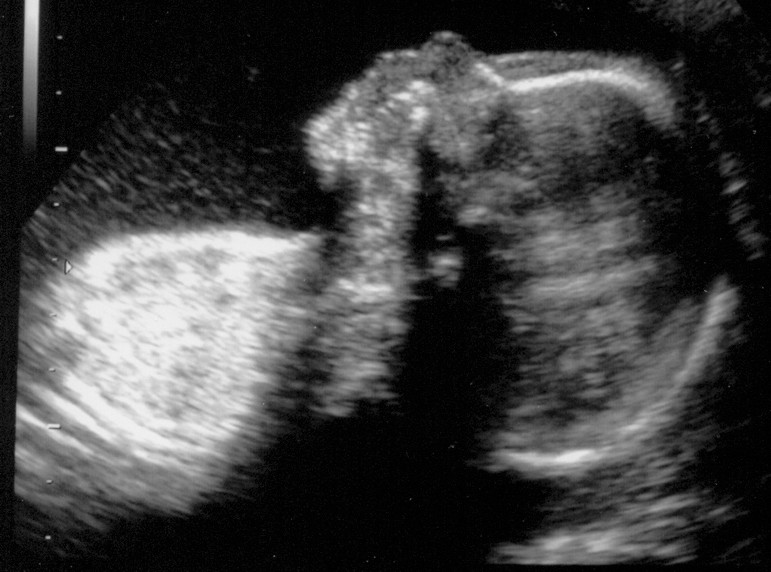

Rechtes Kind im 3D-US

Linkes Kind im "normalen" US

Rechtes Kind im "normalen" US

Eure Bilder sind echt toll. Wenn ich mich jetzt nicht allzu blöd anstelle, seht Ihr gleich das aktuellste von unserem Baby. Mit 3-D kann man schon sehr schön alles erkennen, aber wir haben auch ganz schaurige Bildchen. Kommt immer darauf an, wie die Mäuse posieren. :wink:

Unser "Maikätzchen" am 07.03.06